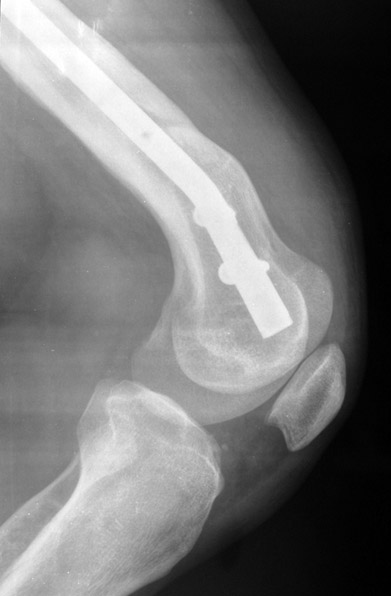

3. POSTTRAUMATIC LOWER LIMB SHORTNESS (MALUNION)

This type of shortness occurs after a fracture heals in a shortened position. Most cases are seen in adults and can be treated with one lengthening operation. Additional deformities can be corrected simultaneously. Most of these cases can be treated with lengthening over nail or just corrections and intramedullary nailing.